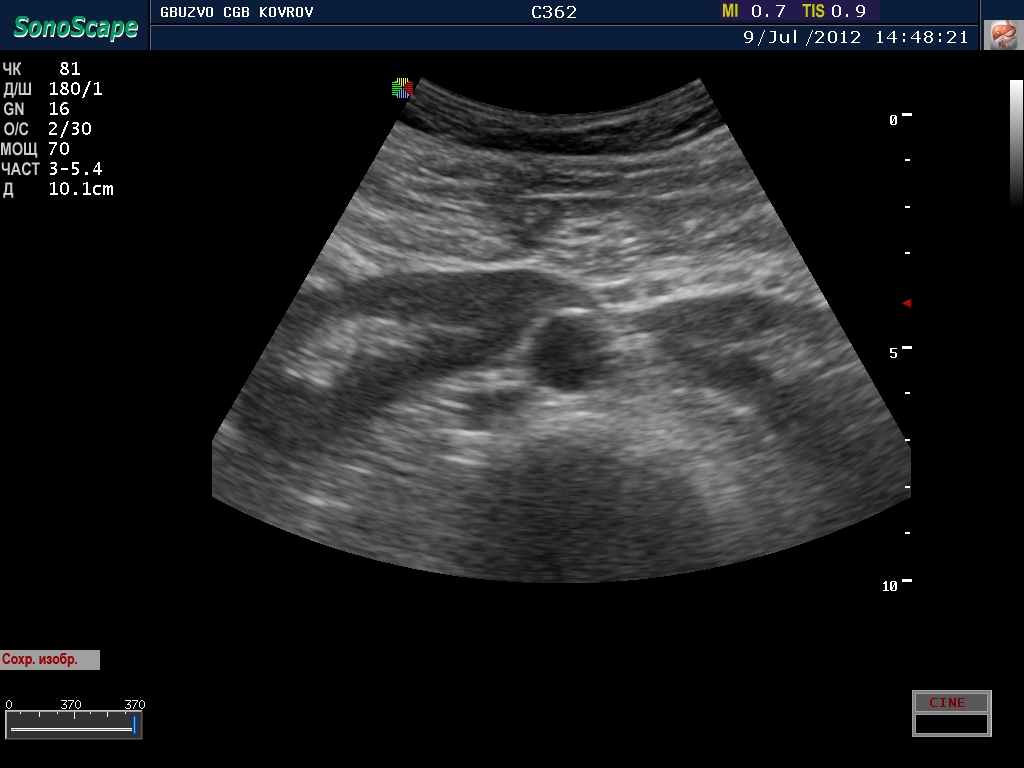

Добавлю с разрешения коллег, свое наблюдение...

Вот нифига себе! Это ребёнок?

:D Почему ребенок, дяденька 45 лет! а что вас смутило?

Расположение. Сгрудились у аорты...

расположение аномальное - подковообразная почка 8-) четко виден перешеек!

В своё время не разъехались. А жить то ему это мешает? Наверное нет.

живет..хлеб жует...нет не мешает.